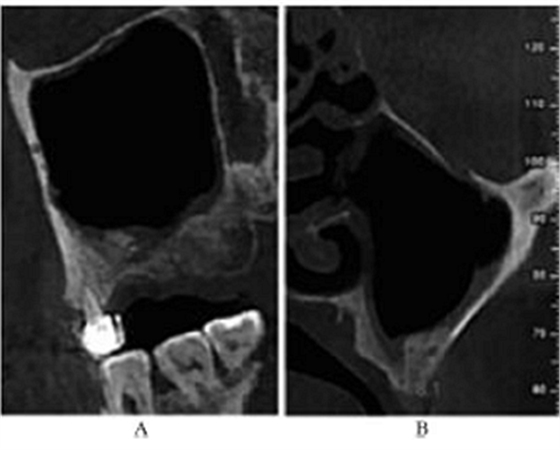

CBCT示:上颌窦内见液平面约达窦腔1/3(考虑为冲洗液未吸干净),上颌窦垂直高度得到补足,26牙高度8.4mm,27牙高度为9.5mm(图3)。患者拒绝穿刺液送病理检查。

图3 上颌窦外提升术后CBCT。

注:A,矢状面;B,26颊舌向切面;C,27颊舌向切面;D,28颊舌向切面。